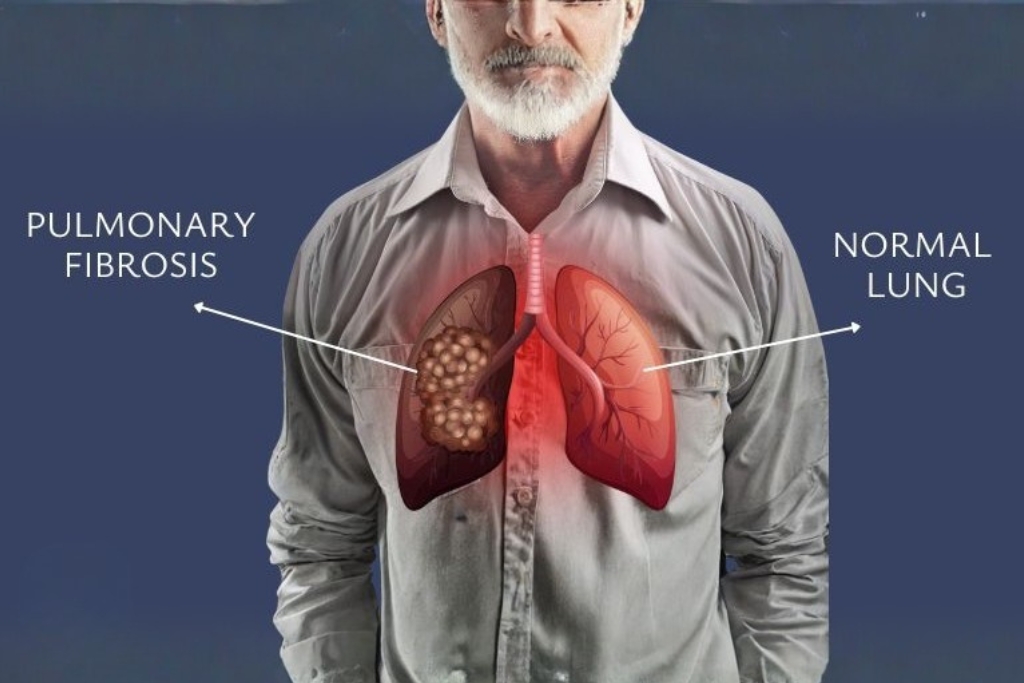

Pulmonary Fibrosis

Pulmonary fibrosis causes progressive scarring of lung tissue, leading to long-term breathlessness and reduced oxygen levels.